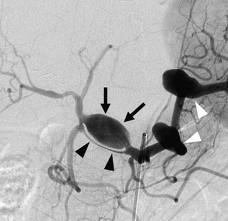

In the case of a fusiform aneurysm, the dilation in the blood vessel looks like a spindle. It is usually a complication of severe atherosclerosis, and is sometimes called an atherosclerotic aneurysm for this reason. Because of the elongated and tortuous shapes of fusiform aneurysms, “dolichoectasia” is another term that has been used to describe them. Diagnosis is performed with the assistance of medical imaging studies, which may include the use of contrast to clearly highlight the vascular system so that abnormalities can be clearly seen on the study.

Unlike the focal outpouchings found in saccular aneurysms, in fusiform aneurysms the entire vessel expands, which supports the observation that deficiency of the muscular wall and internal elastic lamina is diffuse. The circulation slows because of this increased luminal diameter, and the resulting turbulent blood flow predisposes the vessel to thrombosis, which promotes further intimal disruption and vessel distortion. Repeated thrombosis near the wall makes the vessel stiff and thick. The natural tendency then for a fusiform aneurysm is to expand and produce mass effects on nearby structures. Or, the expanding fusiform aneurysm can distort vascular branches, reducing distal flow, or can even serve as a nidus for clot formation and distant embolization.

Symptoms of a fusiform aneurysm vary. Their mass can compress surrounding structures, such as the brain stem. Any fibrofatty thrombus that they contain can fracture, flow through the circulation to other regions of the brain, and cause a stroke. Often, the issue is not identified in the early stages, with problems emerging when the aneurysm is close to rupture and the patient is experiencing symptoms associated with low blood pressure such as dizziness, fainting, and pale skin. The aneurysm may also be identified during medical imaging or routine screening for another medical issue. On imaging scans, these lesions appear as long, wide, serpentine shaped aneurysms.